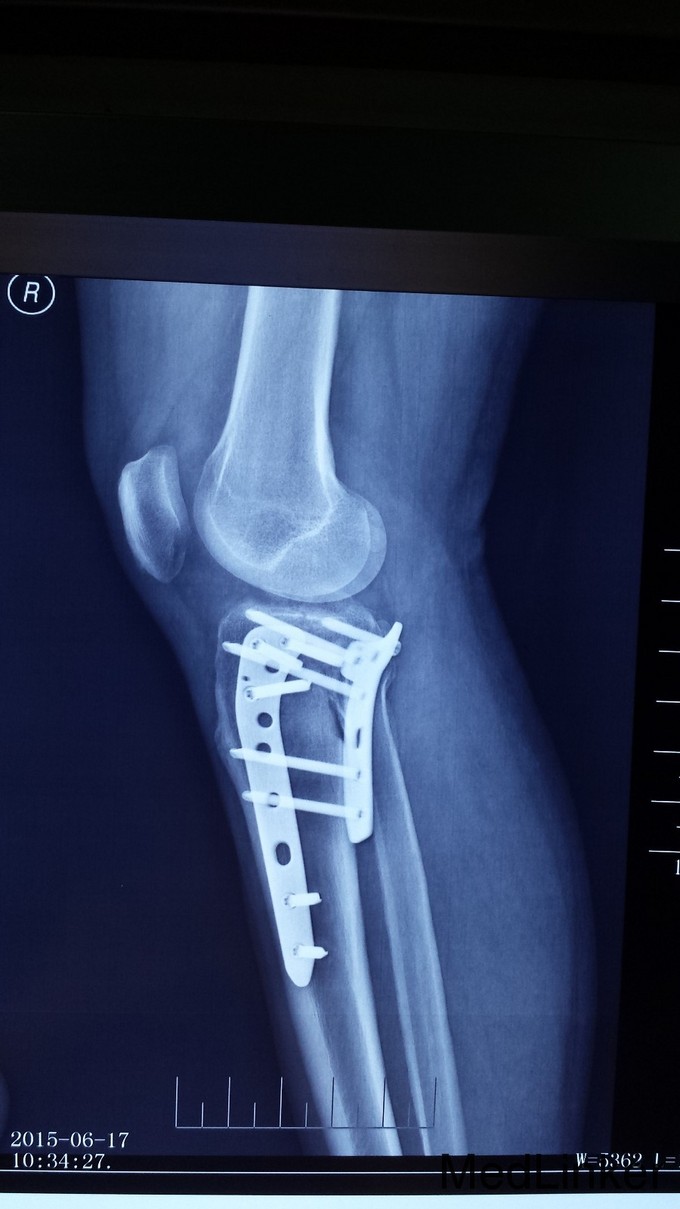

光片提示:患者发生累及后内踝的平台骨折。急诊:施行后内、前外侧联合入路手术治疗。先作后内侧入路复位后内髁骨折块及内髁骨折,再作前外侧联合入路复位外髁骨折,同时处理半月板及前、后交叉韧带损伤。

胫骨平台骨折是较为严重的骨折。如诊治不当,会导致股骨髁向后半脱位,造成膝关节不稳、疼痛、及退行性变,致膝关节功能障碍。因此治疗时要注意关节面解剖复位、坚强内固定及塌陷骨植复位。胫骨平台骨折完全恢复一般需六个月,因此进行功能锻炼要循序渐进。过早或过量运动容易造成平台塌陷。早期应增强无负重的肌肉锻炼,多做坐踢腿动作,促进关节血液循环,帮助恢复。